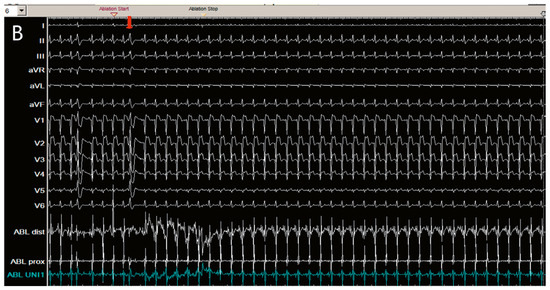

Direct His bundle pacing has recently attracted interest as a more physiological alternative to right ventricular or biventricular stimulation. The advent of new tools has facilitated the implantation procedure. This report relates our initial experi...